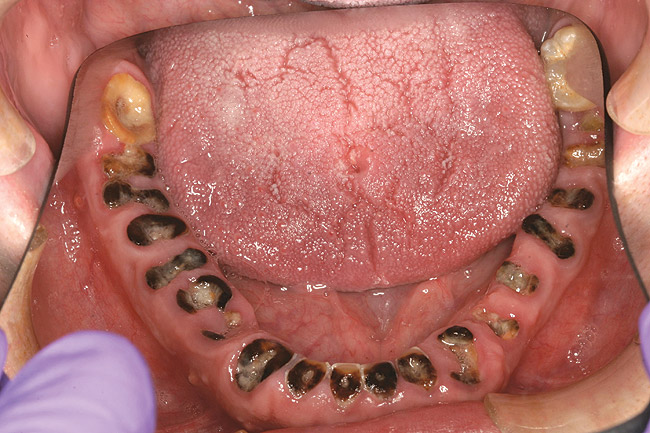

When smoked, methamphetamine produces highly toxic and corrosive fumes of lithium, muriatic, and sulfuric acids that can destroy enamel rapidly. With continued use, methamphetamine can produce severe, rampant caries, similar to early childhood caries. Patients have reported noticing changes in the appearance of tooth structure in as little as 3 months of use. The affected surfaces are the buccal and labial smooth surfaces, as well as the interproximal surfaces (Figure 1 through Figure 3). Because in the general population the vast majority of decay is found in the posterior molars, when someone presents with rampant anterior lesions it should be a red flag for methamphetamine use.5

Figure 1  DEVASTATING EFFECTS When smoked, methamphetamine produces highly toxic and corrosive fumes of lithium, muriatic, and sulfuric acids that can destroy enamel rapidly. With continued use, methamphetamine can produce severe, rampant caries. When someone presents with rampant anterior lesions it should be a red flag for methamphetamine use.

Figure 1

Figure 2  DEVASTATING EFFECTS When smoked, methamphetamine produces highly toxic and corrosive fumes of lithium, muriatic, and sulfuric acids that can destroy enamel rapidly. With continued use, methamphetamine can produce severe, rampant caries. When someone presents with rampant anterior lesions it should be a red flag for methamphetamine use.

Figure 2